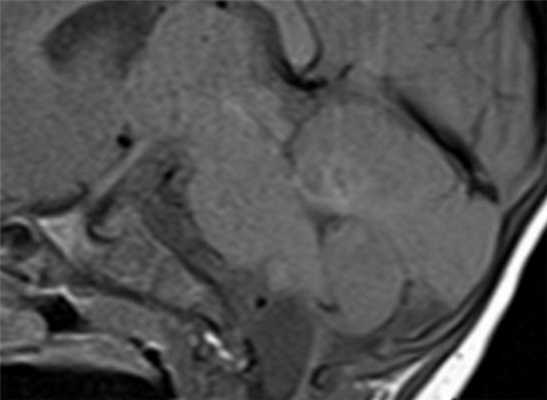

МРТ головного мозга. Корональная Т1-взвешенная МРТ. Многокамерные эхинококковые кисты.